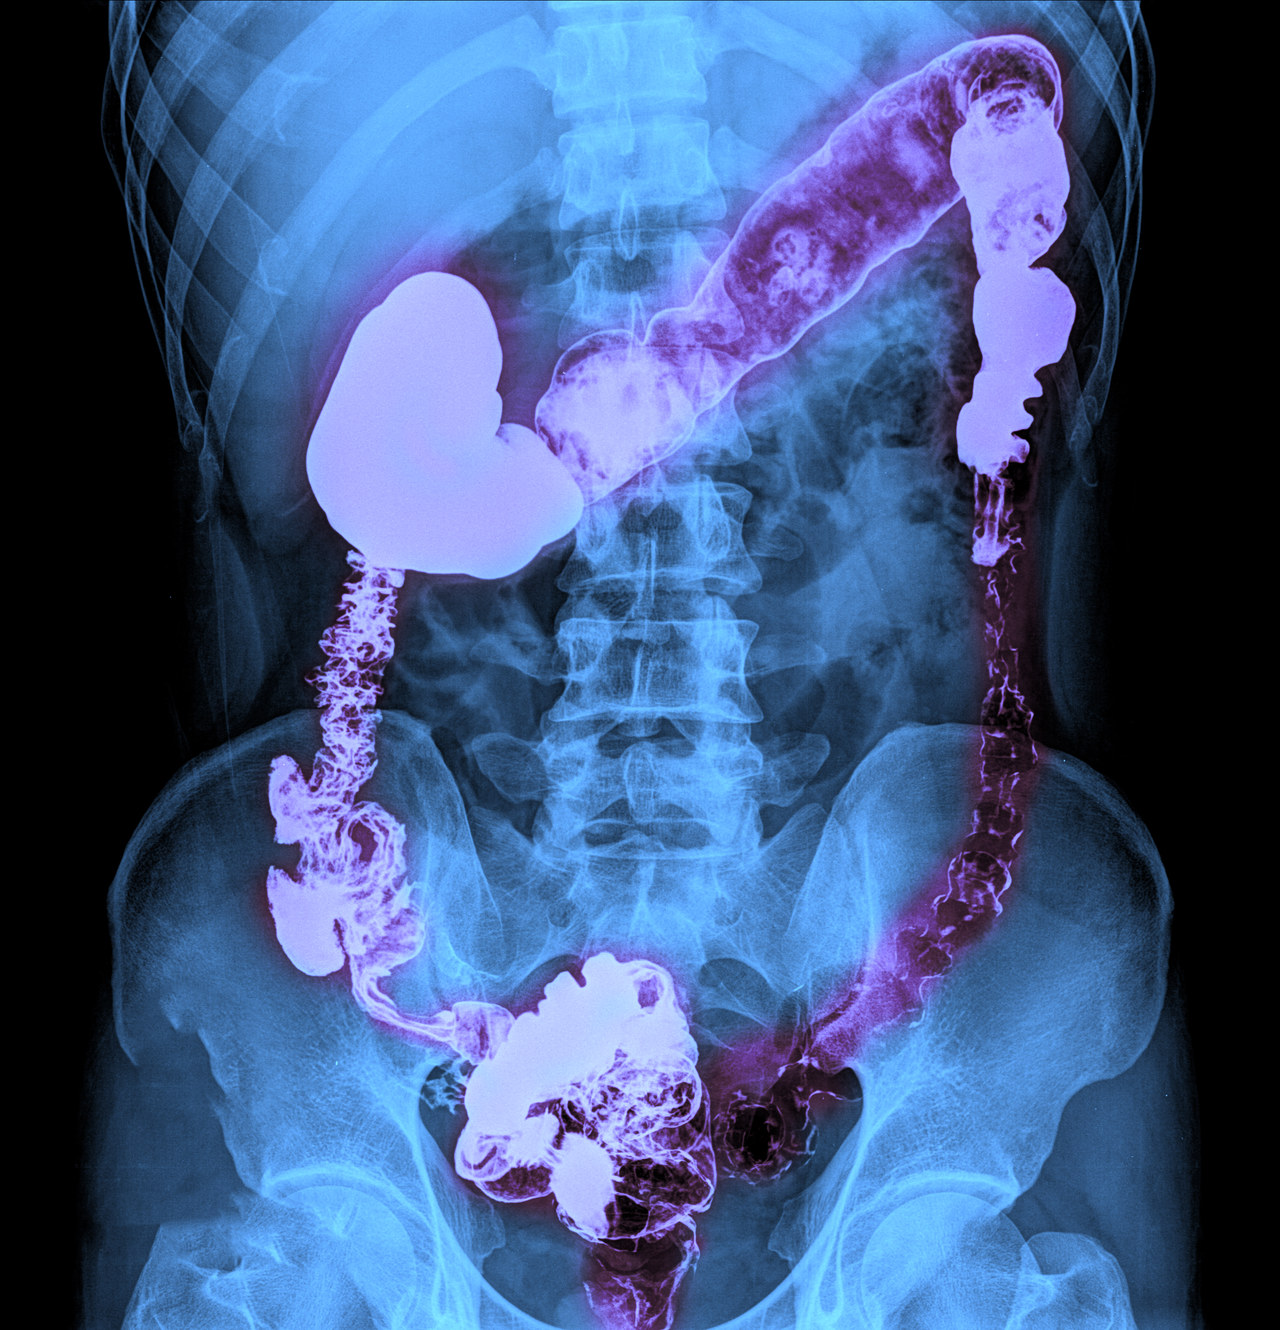

肠道疾病的治疗

肠道疾病种类繁多,治疗方法也因病而异。了解常见的治疗手段,有助于患者更好地配合医生进行治疗,恢复健康。